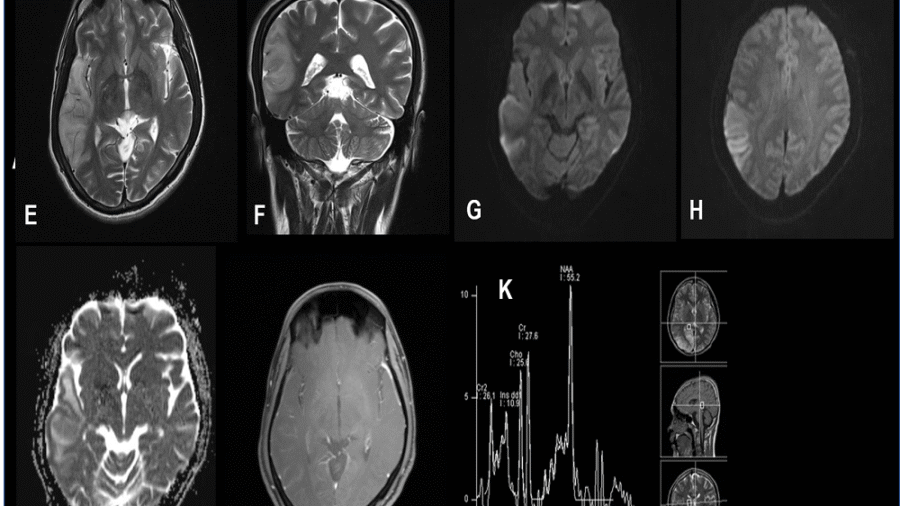

39 years , male, presented with progressive gait disturbance and speech difficulty since 11 months. Associated with headache, giddiness and vomiting since 3-4 months.